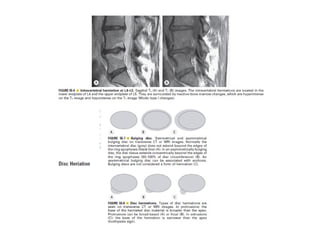

The spine is made up of vertebrae separated by intervertebral discs that allow movement and provide shock absorption. Diagnostic imaging plays an important role in evaluating the spine for conditions like fractures, disc herniations, spinal stenosis, and tumors. Imaging modalities like X-rays, CT scans, MRI, and bone scans can detect abnormalities and aid physicians in diagnosing and treating various spinal disorders.